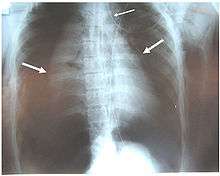

Chest x-ray is the initial imaging technique used to diagnose TBI.[9] The film may not have any signs in an otherwise asymptomatic patient.[13] Indications of TBI seen on radiographs include deformity in the trachea or a defect in the tracheal wall.[9] Radiography may also show cervical emphysema, air in the tissues of the neck.[2] X-rays may also show accompanying injuries and signs such as fractures and subcutaneous emphysema.[2] If subcutaneous emphysema occurs and the hyoid bone appears in an X-ray to be sitting unusually high in the throat, it may be an indication that the trachea has been severed.[4] TBI is also suspected if an endotracheal tube appears in an X-ray to be out of place, or if its cuff appears to be more full than normal or to protrude through a tear in the airway.[9] If a bronchus is torn all the way around, the lung may collapse outward toward the chest wall (rather than inward, as it usually does in pneumothorax) because it loses the attachment to the bronchus which normally holds it toward the center.[6] In a person lying face-up, the lung collapses toward the diaphragm and the back.[10] This sign, described in 1969, is called fallen lung sign and is pathognomonic of TBI (that is, it is diagnostic for TBI because it does not occur in other conditions); however it occurs only rarely.[6] In as many as one in five cases, people with blunt trauma and TBI have no signs of the injury on chest X-ray.[10] CT scanning detects over 90% of TBI resulting from blunt trauma,[3] but neither X-ray nor CT are a replacement for bronchoscopy.[6]